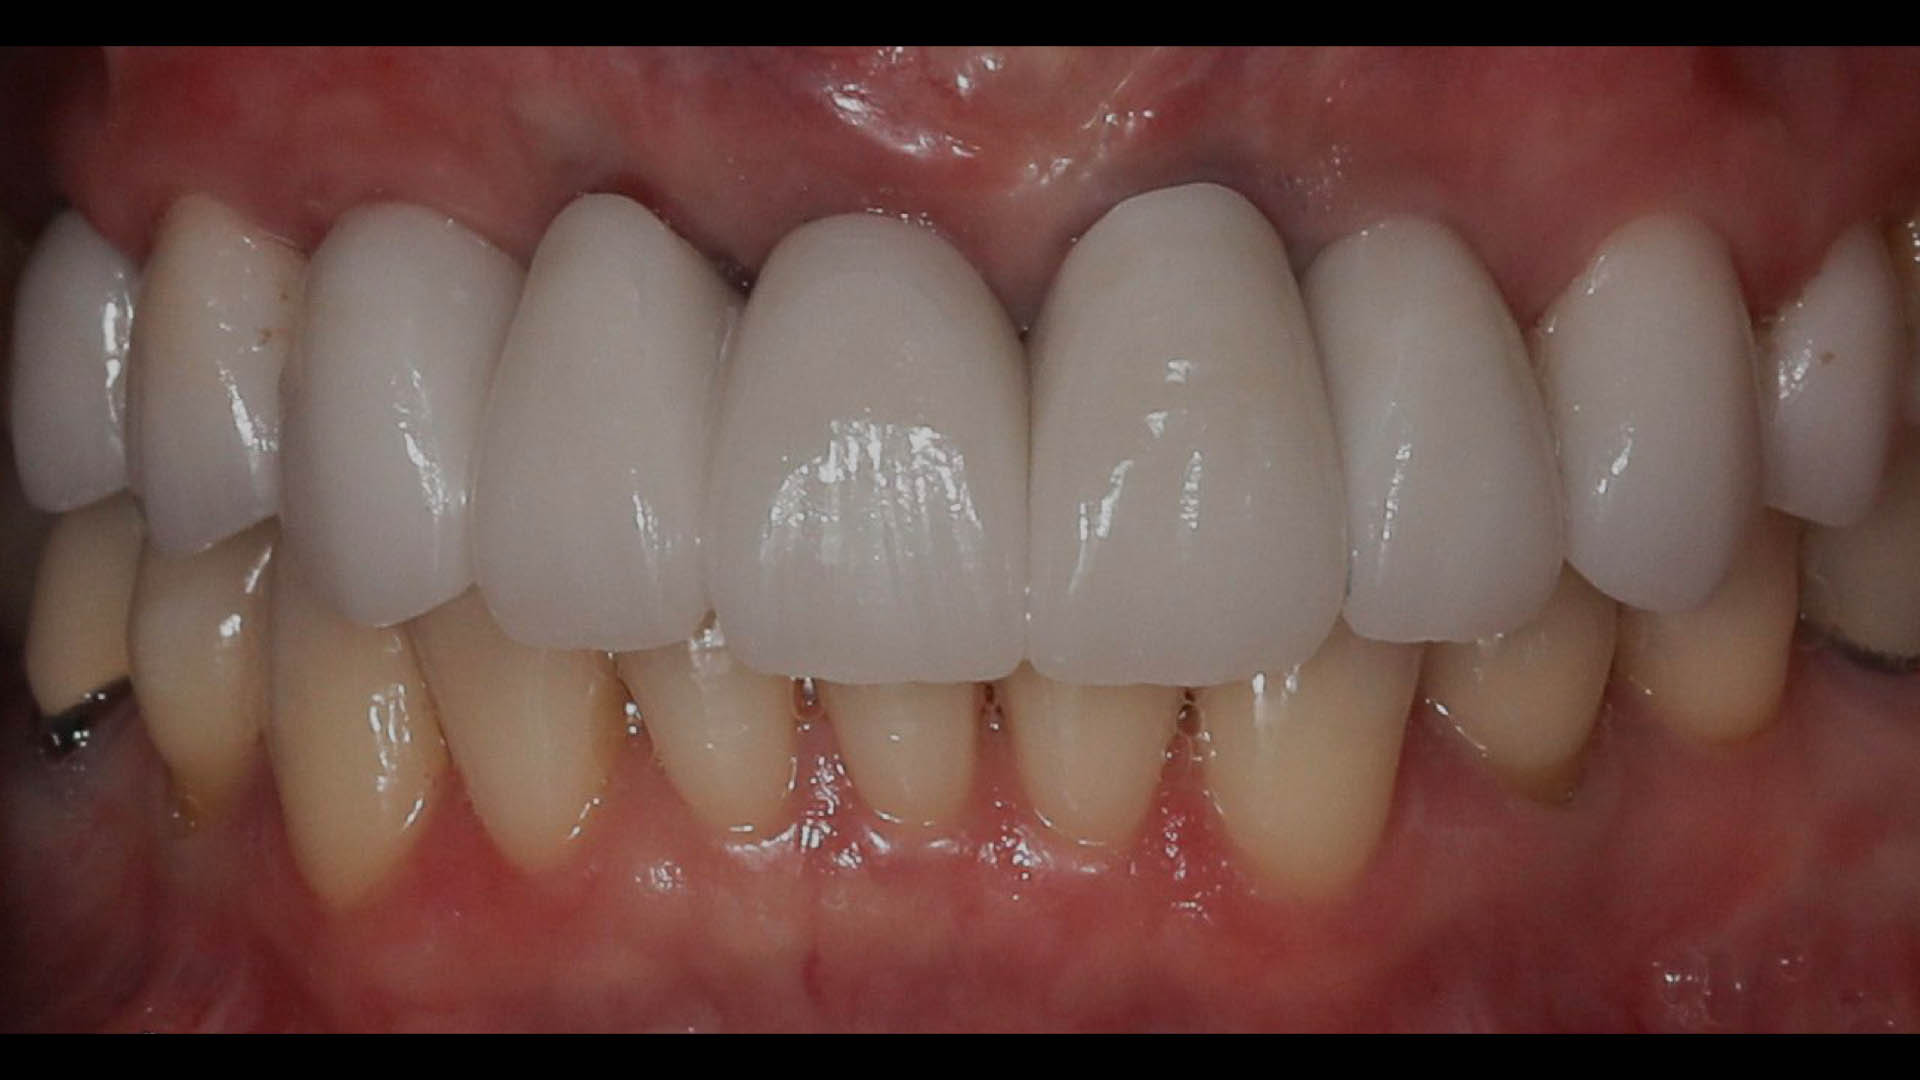

Take a glimpse into the magic of Coral Gables Dentistry through our before and after pictures. See firsthand the incredible smile makeover transformations that have brought confidence and joy to our patients.